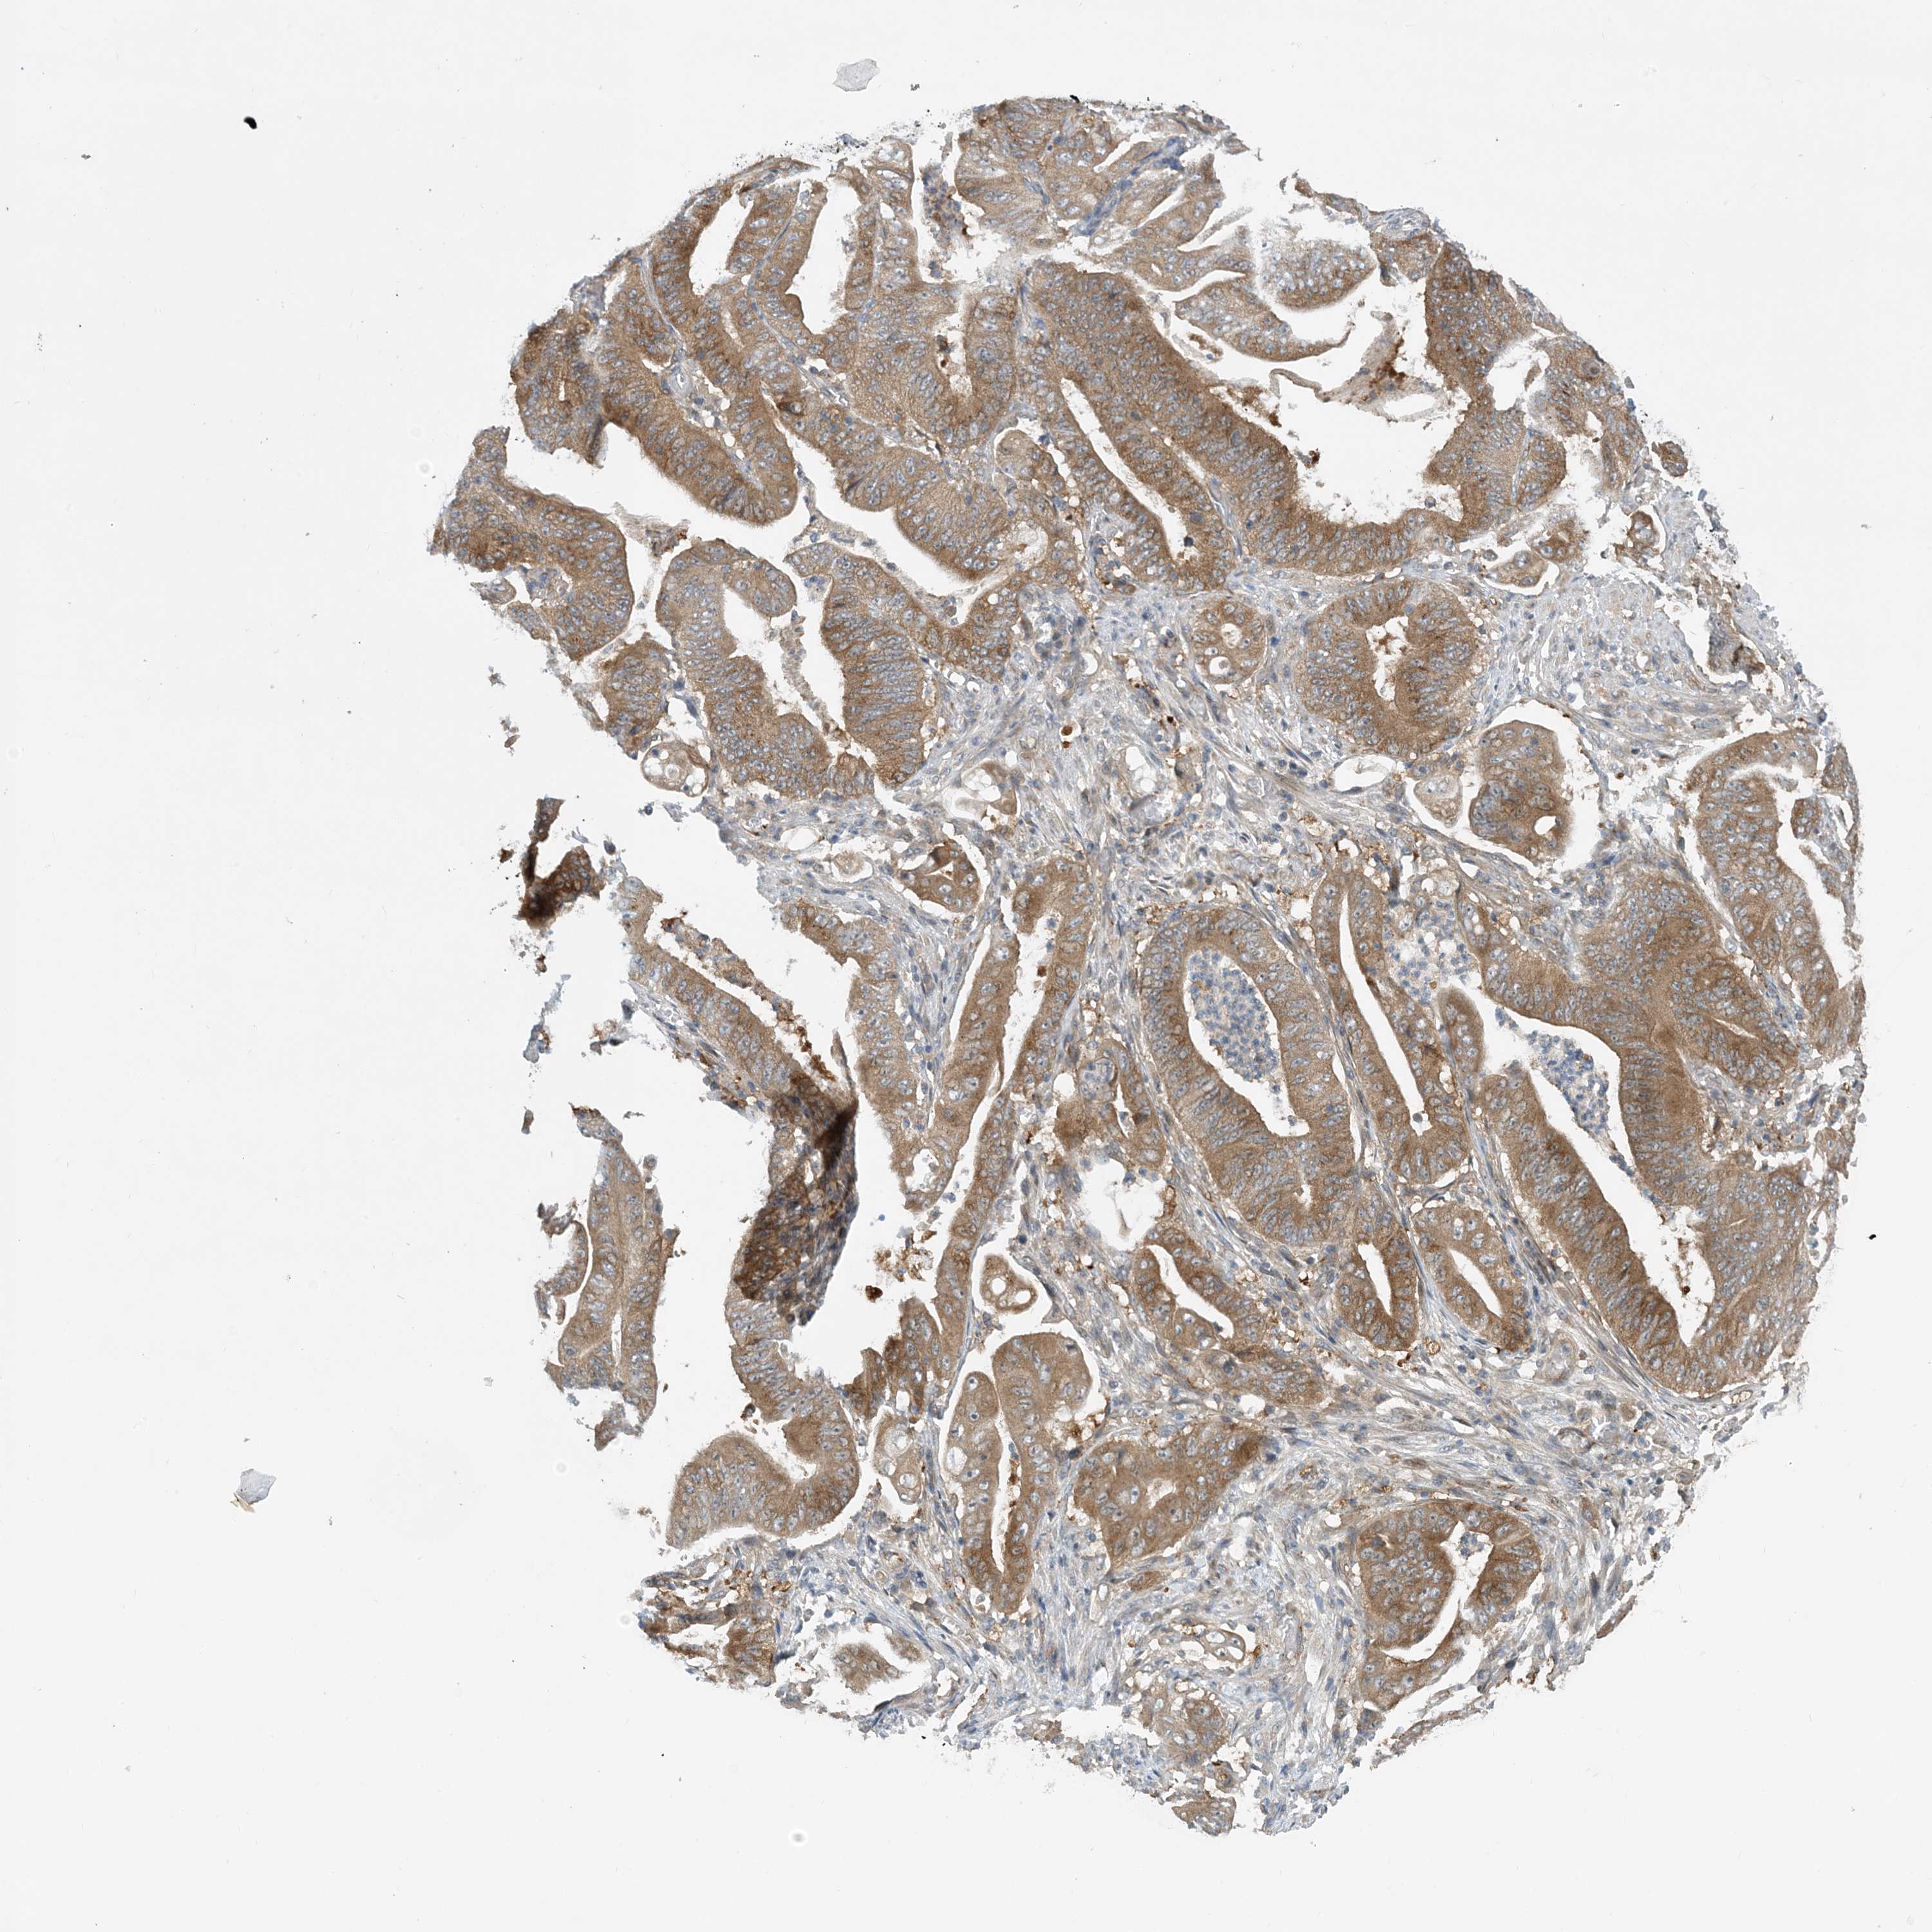

STOMACH CANCER - Protein expressioni

A mouse-over function shows sample information and annotation data. Click on an image to view it in a full screen mode. Samples can be filtered based on level of antibody staining by selecting one or several of the following categories: high, medium, low and not detected. The assay and annotation is described here.

Note that samples used for immunohistochemistry by the Human Protein Atlas do not correspond to samples in the TCGA dataset.

Antibody stainingi

Antibody staining in the annotated cell types in the current human tissue is reported as not detected, low, medium, or high, based on conventional immunohistochemistry profiling in selected tissues. This score is based on the combination of the staining intensity and fraction of stained cells.

Each image is clickable and will lead to virtual microscopy that enables deeper exploration of all samples and also displays staining intensity scores, fraction scores and subcellular localization as well as patient and tissue information for each sample.

Antibody HPA035427

Antibody HPA073753

Staining

High

Medium

Low

Not detected

Intensity

Strong

Moderate

Weak

Negative

Quantity

>75%

75%-25%

<25%

None

Location

Nuclear

Cytoplasmic/membranous

Cytoplasmic/membranous,nuclear

Adenocarcinoma, NOS

Adenocarcinoma, High grade